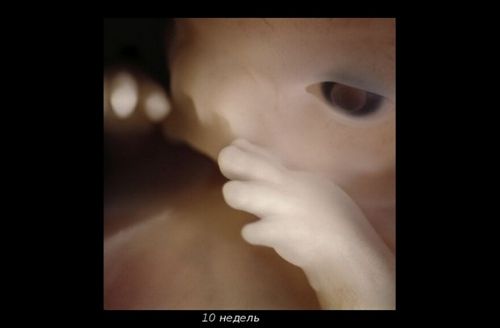

Малюк починає робити перші рухи в маминому животі, однак відчути їх поки неможливо. Тільки акушер через стетоскоп можна почути серцебиття ненародженої крихти. Скоро завершитися "дозрівання" діафрагми, і вона буде брати активну участь в диханні. Замість «хвостика» з'являються сідниці.

Можна добре розглянути личко малюка. Як думаєте, він схожий на тата? Дитина активно моргає, відкриває ротик і удосконалює хапальний рефлекс.